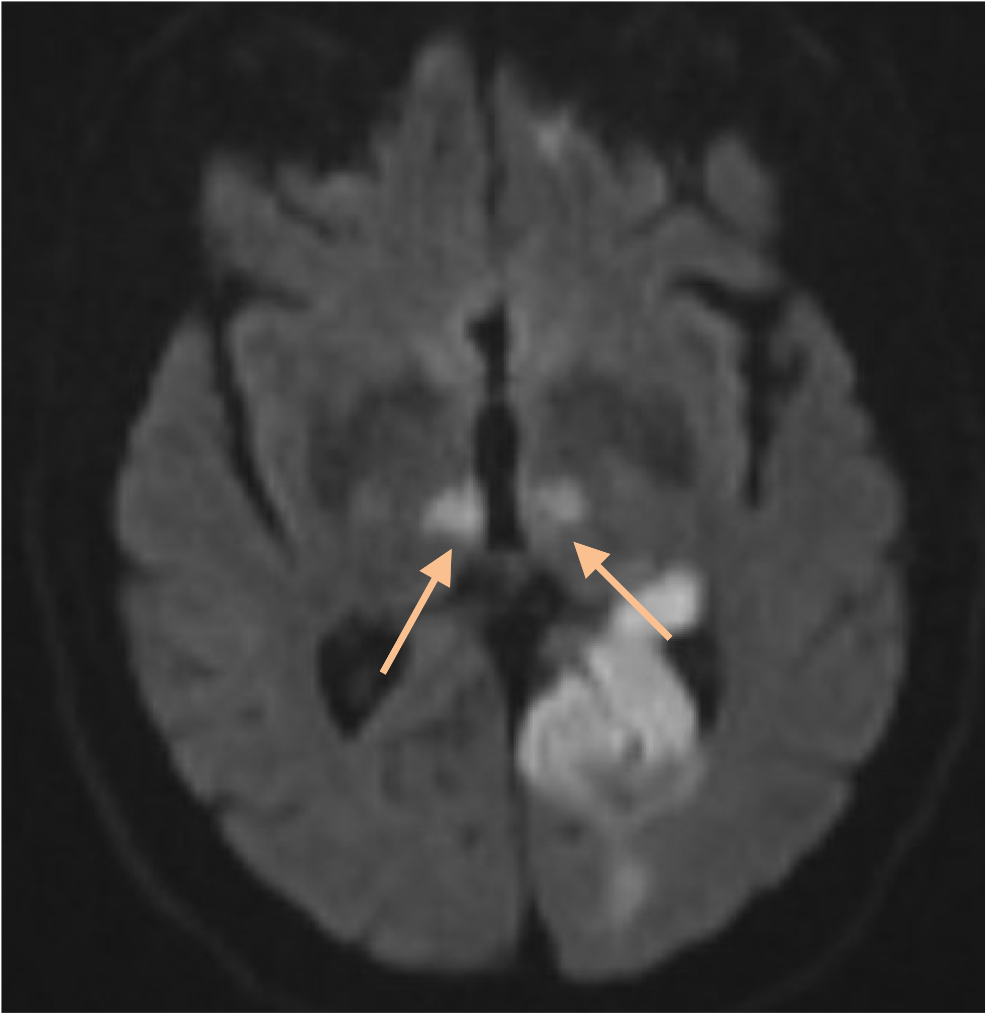

Occlusion of which vessel(s) cause this stroke?

Artery of Percheron